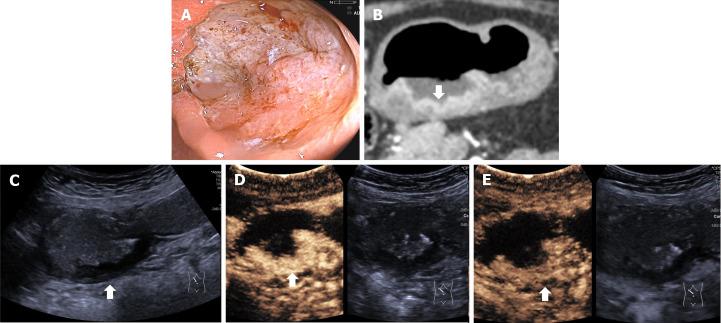

This single prospective study enrolled patients with GC confirmed by preoperative gastroscopy from July 2021 to March 2023. Patients underwent DCEUS, including ultrasonography (US) and intravenous contrast-enhanced ultrasonography (CEUS), and MDCT examinations for the assessment of preoperative T staging. Features of GC were identified on DCEUS and criteria developed to evaluate T staging according to the 8 edition of AJCC cancer staging manual. The diagnostic performance of DCEUS was evaluated by comparing it with that of MDCT and surgical-pathological findings were considered as the gold standard.

A total of 229 patients with GC (80 T1, 33 T2, 59 T3 and 57 T4) were included. Overall accuracies were 86.9% for DCEUS and 61.1% for MDCT ( < 0.001). DCEUS was superior to MDCT for T1 (92.5% 70.0%, < 0.001), T2 (72.7% 51.5%, = 0.041), T3 (86.4% 45.8%, < 0.001) and T4 (87.7% 70.2%, = 0.022) staging of GC.